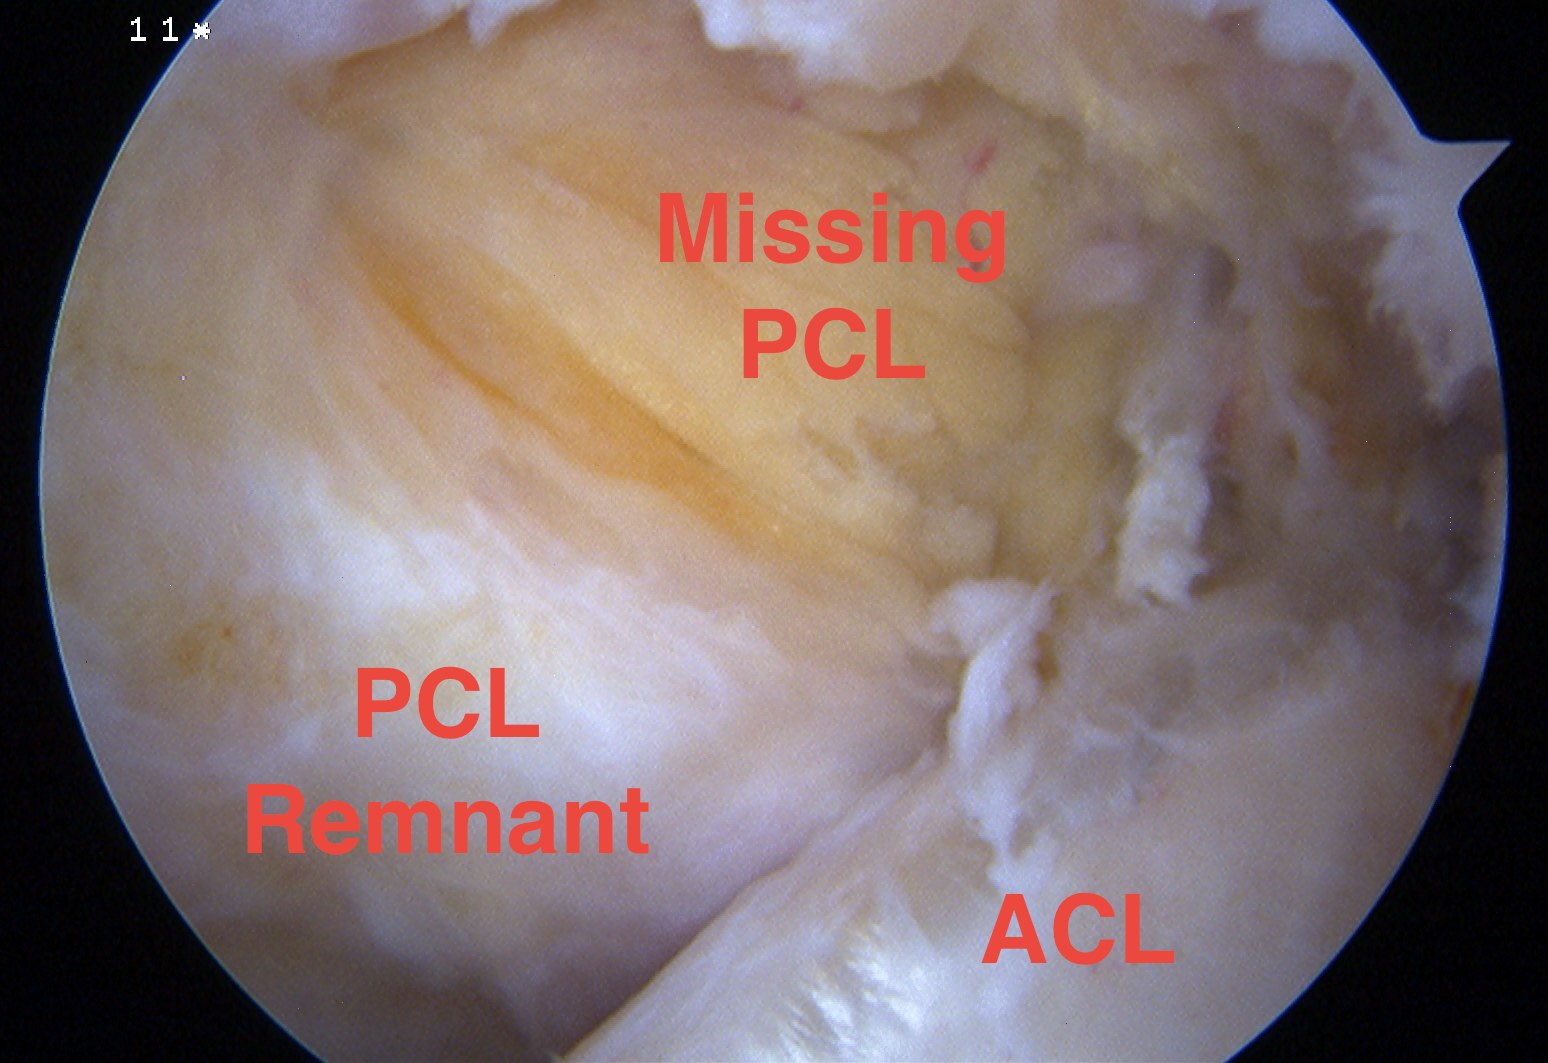

Arthroscopy

May miss tear as is extra-synovial

Chronic PCL tear from femur

Acute PCL femoral avulsion

Apparent ACL laxity due to PCL tear and posterior tibial sag; ACL tension restored with anterior drawer